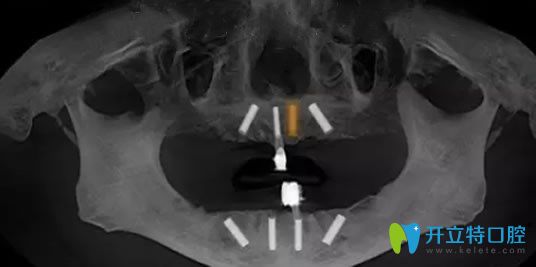

恢復(fù)了三個(gè)多月,經(jīng)過邱院長口腔檢查確認(rèn)無誤,就為老媽實(shí)施了ALL-on-4種植牙,利用四顆種植體為老媽種出整排牙齒,種植體的減少,避免了多次手術(shù),操作簡單,減少了手術(shù)創(chuàng)傷,手術(shù)時(shí)間短,種牙無需植骨,即種即用,讓老媽擁有了整齊潔白的牙齒,露出了燦爛的笑容。

寧波美萊口腔牙齒缺失種植牙恢復(fù)效果圖: